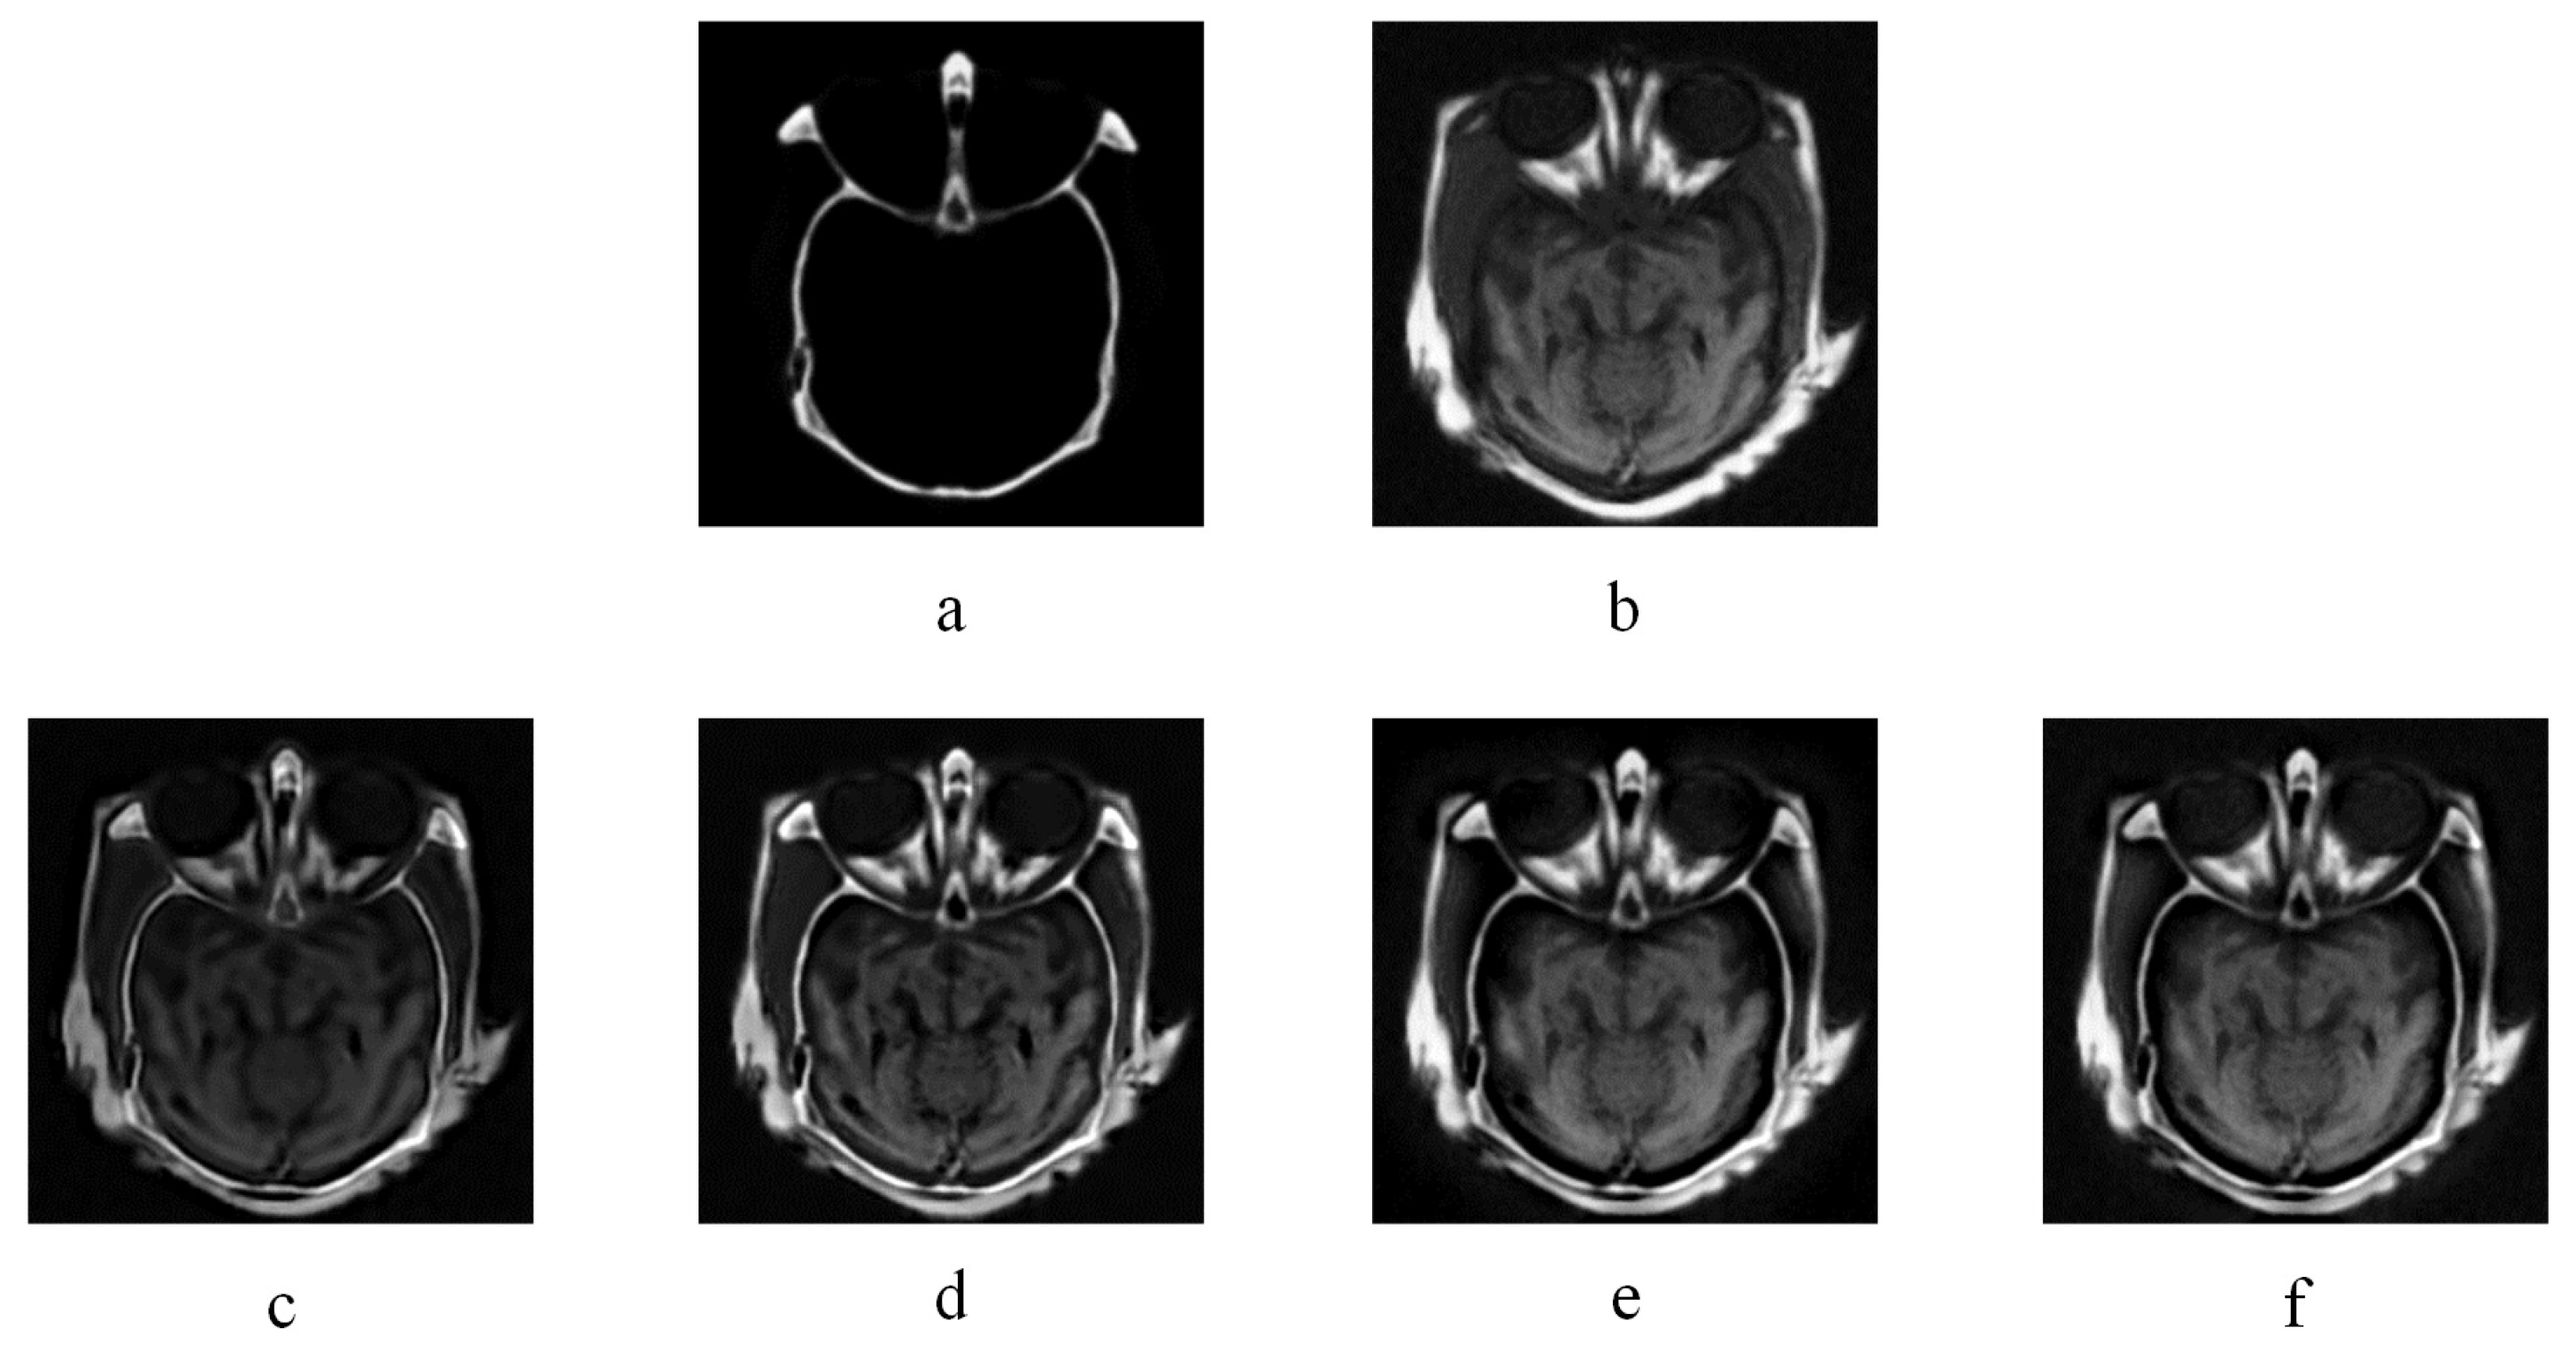

3.2.1. Experiment Results of Medical Images